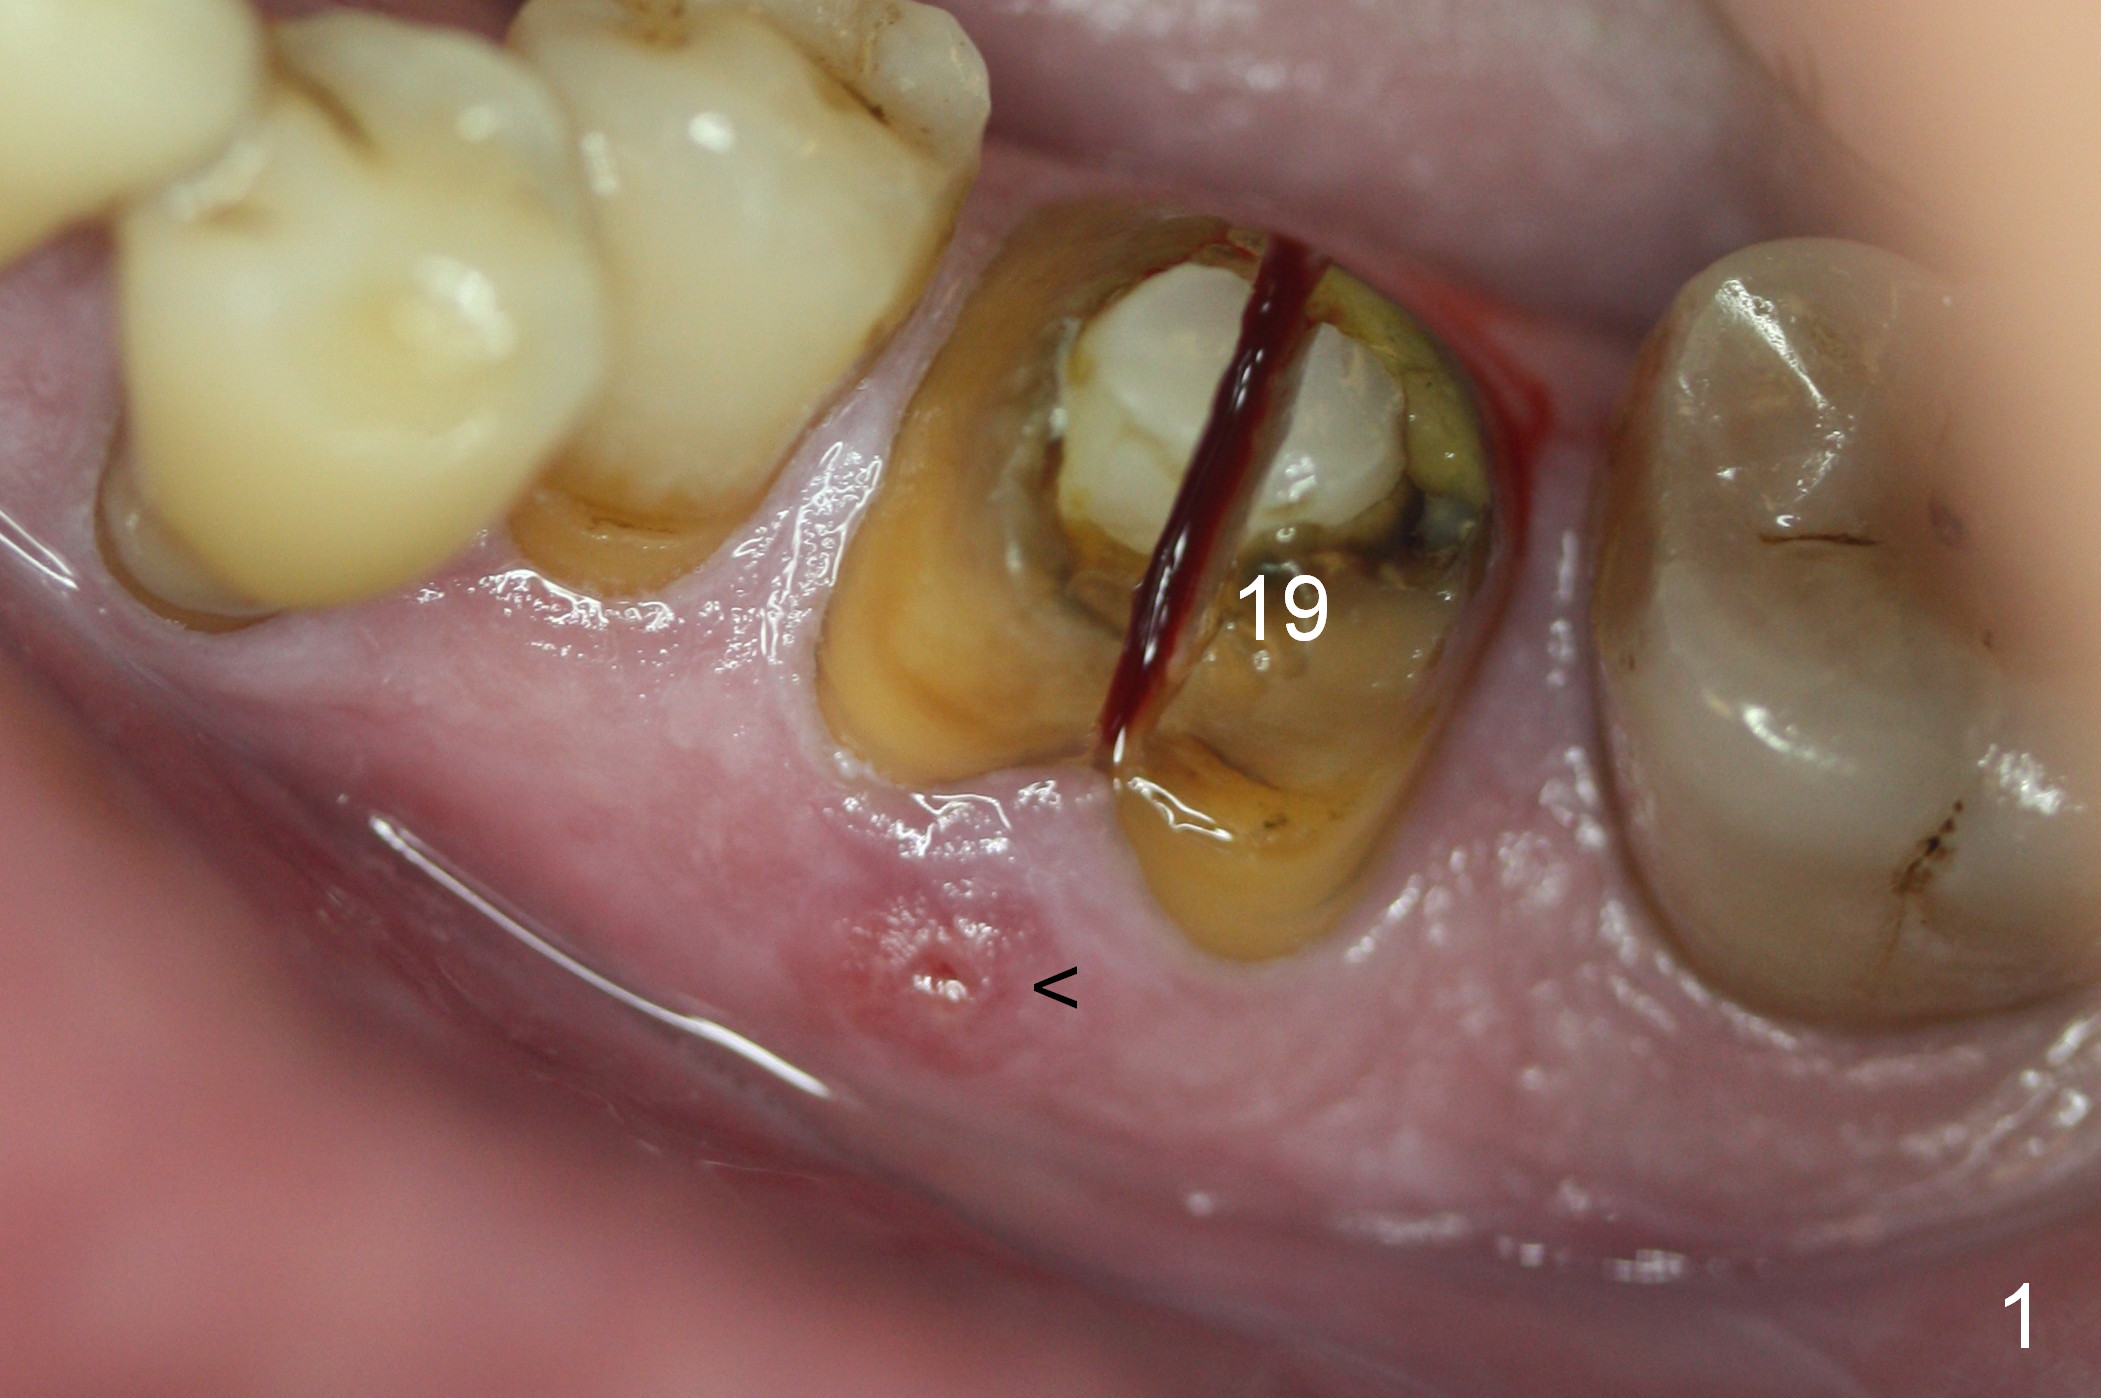

A fistula is found to be associated with the furca when the patient returns for extraction (Fig.1 <). Although the mesial socket is deeper than the distal one, no granulation tissue is curetted from the mesial. Osteotomy is set in the middle of the septum by making a slot first. When the osteotomy is enlarged by 4 mm reamer (Fig.2 R), the latter has been deviated mesial to the septum (*). By manipulating, the coronal end of 6x12 mm implant and 6.5x4(3) mm abutment (Fig.3 A) are placed somewhat in the middle of the socket. An immediate provisional is fabricated to cover the socket and bone graft (Fig.4 P). The exposed bone graft (Fig.4 *) is then covered by perio dressing. Off axial placement of the implant (Fig.5 I) and abutment (A) is striking in the immediately postop PA (Fig.5).